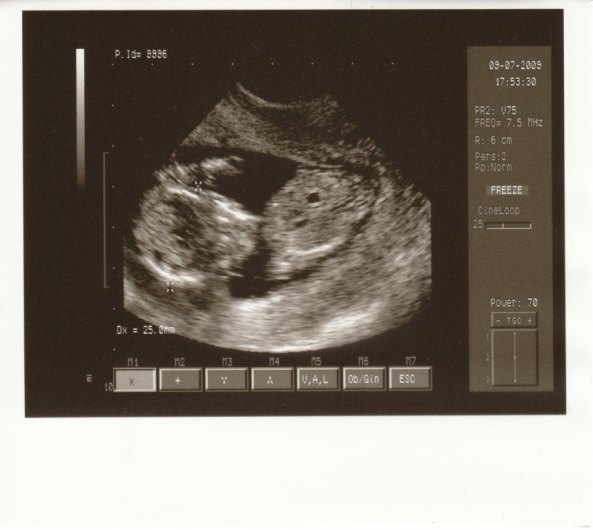

Milyen szégyenlősek ezek a bébik...Én is olyan türelmetlen vagyok már.Ha aug. 5-én sem derül ki a neme, addig megyek , amíg valaki meg nem mondja...